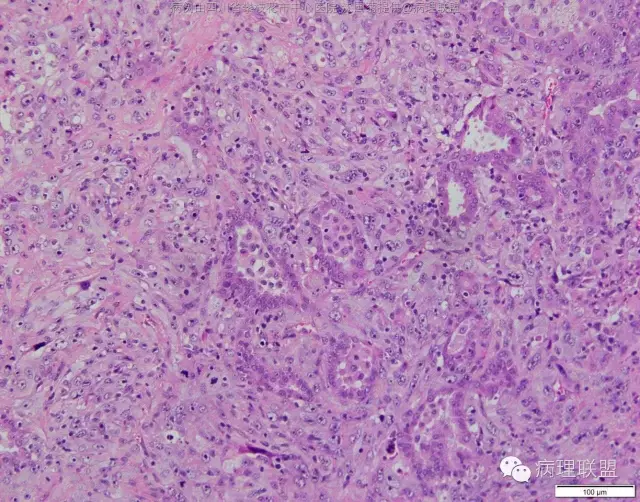

M/47 肺部占位,大小2*1*0.6cm(病例由四川攀枝花市中心医院 沈国菊提供,致谢!)

@张丽 免疫组化腺癌,鳞癌,神经内分泌,恶黑标记均为阴性,只有广谱CK跟Vimentin阳性,准备发大细胞癌

@沈国菊 肺大细胞癌的签发有时是个排他性诊断,我的体会:大细胞的标准:按淋巴细胞直径3倍来算,需要大于这个值,不能等于(从图给出,符合)。神经内分泌的标记(CD56 SYN CgA)完全阴性的可能性不是没有,建议重做试试;细胞的异型性大(符合);Ki67的指数高,应该非常高(您这里没有给出)。这仅仅是我个人体会,我说的不一定正确。

感谢您的精彩病例,采图非常漂亮,并且有标尺(特别赞)。魏老师,Ki-67阳性大于90%,送检7组淋巴结6/7见肿瘤转移。